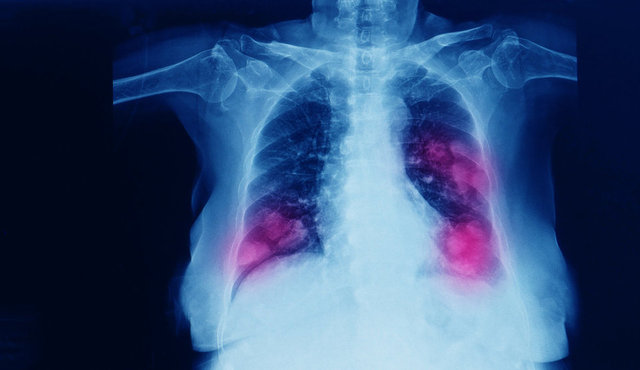

Tıbbi Onkoloji Uzmanı Prof. Dr. Özlem Er, erken tanı için risk faktöründeki kişilerin inatçı öksürükte mutlaka hekime başvurmaları gerektiğine dikkat çekerek, “Ayrıca hiçbir şikayeti olmasa dahi risk faktöründe olan 40 yaş üstündeki kişilerin her yıl düzenli olarak düşük doz bilgisayarlı akciğer tomografisiyle mutlaka taranmaları gerekiyor. Zira akciğer kanseri en çok hayat kaybına yol açan kanser tiplerinden biri olmasına rağmen erken tanı sayesinde tümöre özel tedavi protokolü ile hastalar uzun yıllar sağlıklı ve aktif yaşamlarına devam edebiliyor” dedi.

TEDAVİ HASTAYA ÖZEL PLANLANIYOR

Akciğer kanseri temel olarak ‘küçük hücreli olan’ ve ‘küçük hücreli olmayan’ şeklinde iki gruba ayrılıyor. Tedavi akciğerde gelişen tümörün tipi ve evresine göre planlanıyor. Prof. Dr. Özlem Er, hastaya özel uygulanan protokol sayesinde tedaviden oldukça başarılı sonuçlar alındığına işaret ederek, “Küçük hücreli akciğer kanserinde kemoterapi tedavinin en önemli parçasını oluşturuyor. Bunun nedeni ise bu yöntemin hızla çoğalan hücrelerde etkili olması. Erken evre akciğer kanseri kemoterapi ve radyoterapinin birlikte uygulanmasıyla tedavi ediliyor. Yaygın evrede ise kemoterapi ve temelde bağışıklık sisteminin güçlendirilmesini amaçlayan immunoterapi kombinasyonuyla tedavinin başarısı artıyor. Küçük hücreli olmayan akciğer kanseri moleküler özellikleri farklı olan birçok hastalığı içerdiği için tümöre özel en uygun tedavi yöntemi seçiliyor” dedi.